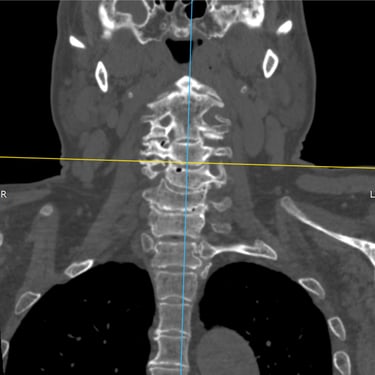

🧠 Fractura vertebral lumbar – Artrodesis con tornillos transpediculares (FTP) canulados y fenestrados, con cementación ósea, asistida con monitoreo neurofisiológico, control radiográfico y neuronavegación.

La fractura vertebral lumbar puede generar inestabilidad severa. La artrodesis con tornillos canulados y fenestrados con cementación ósea, asistida por monitoreo neurofisiológico, control radiográfico y neuronavegación, proporciona una fijación segura, mejora la estabilidad vertebral y reduce el riesgo de complicaciones neurológicas.